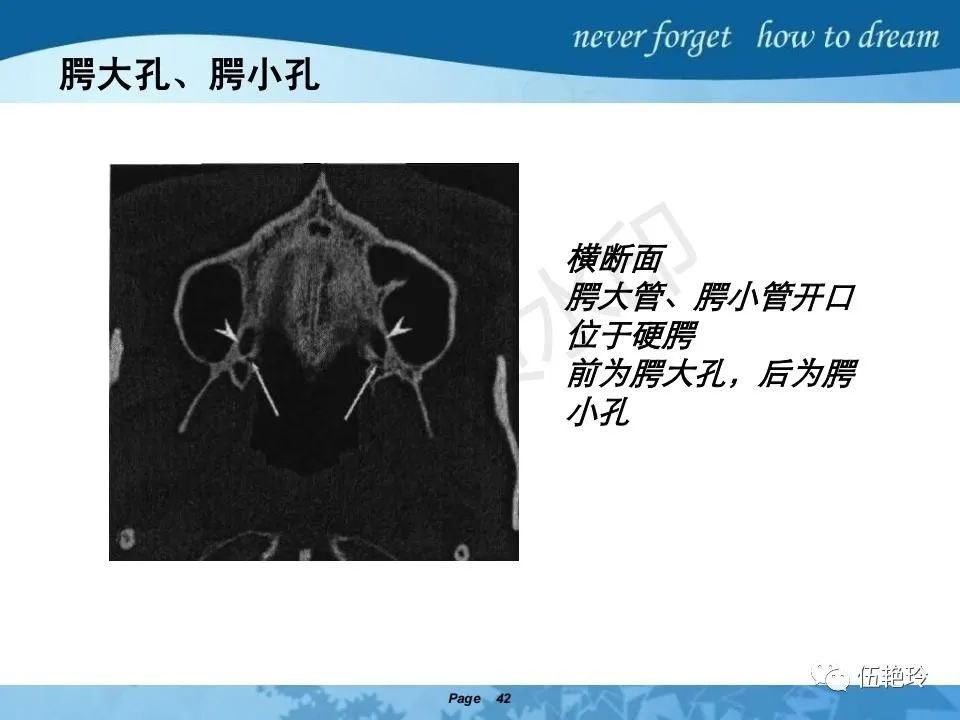

鼻咽癌相关解剖结构

翼腭窝的解剖结构与鼻咽癌侵犯